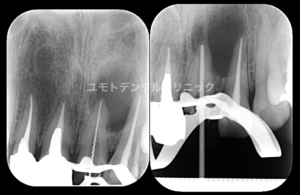

当院では術前の診査時に他の検査とともに複数枚のレントゲン撮影を行います。

通常、対象歯に対し照射角度を変えて2枚のデンタルを撮影いたします。

複数枚のレントゲンから得られる情報は非常に多く、治療を行う際に有効に活用していきます。

下の3枚のレントゲンは右下6番をそれぞれ照射角度を変えて撮影を行ったものになります。

(当時 正方線、偏近心撮影を行い、ポスト部周囲に疑問を感じ偏遠心撮影を加えて行っています。)

分岐部の透過像が初めて確認されたこと、既存のポストを3次元的に確認することができました。

ポスト周囲にはパーフォレーションなどはありませんでしたが、遠心根管内側にストリップパーフォレーション部があり、パーフォレーションリペアを行っております。

短期予後にはなりますが、予後観察時に症状の再発もなく分岐部の透過像の縮小傾向も確認できました。